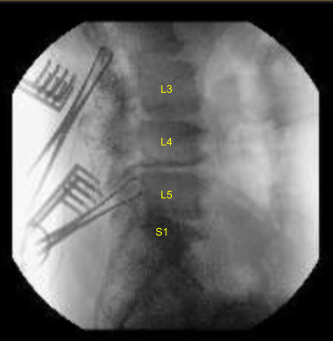

An incision was given along the same incision. With sharp dissection, the spinal process could be reached. With Bovie and blunt dissection, the spinous processes of L2 to S1 were exposed bilaterally onto the facet joint with exposure of the TPs on L2, L3, L4, L5 and sacral ala on both sides. Allis clamp was put on the right L2 and L5 and localization was done with the use of x-ray and found to be in the correct position.

The navigation was brought in and CT scan was performed. After the navigation was verified, pedicle screws were put on both sides of L2 to S1 sequentially under navigational guidance after using gear shift, tapped and checked every time with a ball tip probe.

Posterior osteotomies of the lamina and the inferior facet as well as superior facet were done over the right L5-S1, left L4-5, right L2-3 as well as bilateral L3-4. Complete laminectomy was done over L3-4 along with and bilateral foraminotomy of L3-4 was performed followed by laminotomy and foraminotomy of right L5-S1, left L4-5 and right L2-3.

Annulotomy and thorough discectomy was performed on L2-3 from the right, L3-4 from the left, L4-5 from the left and L5-S1 sequentially with the use of paddles and curettes.

Thorough discectomy was performed and disc was removed with a pituitary. Interdiscal space were irrigated and drained and packed with local autograft bone and Expandable cages packed with bone, were inserted one disc space at a time and expanded in acceptable position under fluoroscopic guidance.